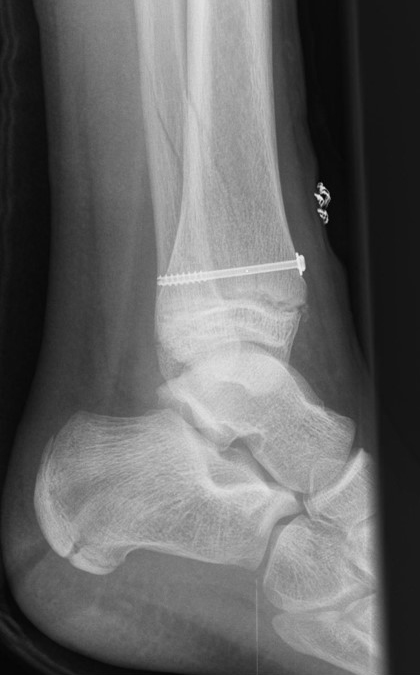

Behandlungsziel ist die exakte Rekonstruktion der Gelenkfläche sowie die Minimierung des Risikos einer späteren Wachstumsstörung. Dislozierte Frakturen werden offen reponiert, die Osteosynthese erfolgt mit einer Kleinfragmentschraube. Finden sich viele kleine Fragmente kann eine K-Draht Osteosynthese durchgeführt werden. Wird der Innenknöchel operiert, kann bei gleichzeitiger hochgradiger lateraler Instabilität eine Rekonstruktion des lateralen Bandapparats durchgeführt werden. Fibula Frakturen stellen sich meist spontan ein, sodass hier keine zusätzliche Osteosynthese notwendig ist.

Nach der Osteosynthese wird die Fraktur für ca. vier Wochen in einem Unterschenkelgips ruhiggestellt. Bei Schmerzfreiheit der Frakturzone erfolgt anschließend eine schmerzadaptierte Belastungssteigerung über weitere zwei Wochen. Sobald unter Alltagsbedingungen Beschwerdefreiheit besteht kann die sportliche Belastung langsam gesteigert werden. Kirschnerdrähte werden 6-8 Wochen postoperativ, Schrauben nach zwölf Wochen entfernt. Es empfiehlt sich klinische und radiologische Kontrollen im Abstand von 6 Monaten bis zum Wachstumsabschluss durchzuführen, um ein mögliches Fehlwachstum frühzeitig zu erkennen.